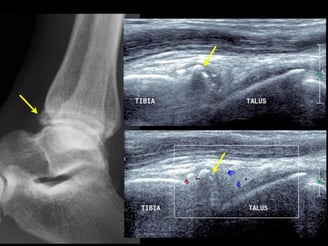

Genoux/ Chevilles et pieds